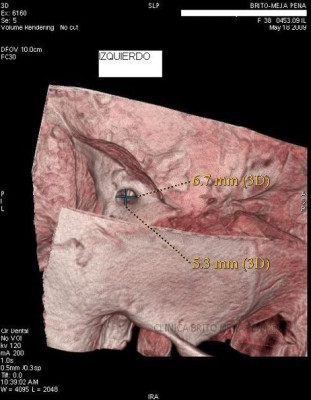

Envíado por BMP Imágenes Diagnósticas

BMP Imágenes Diagnósticas